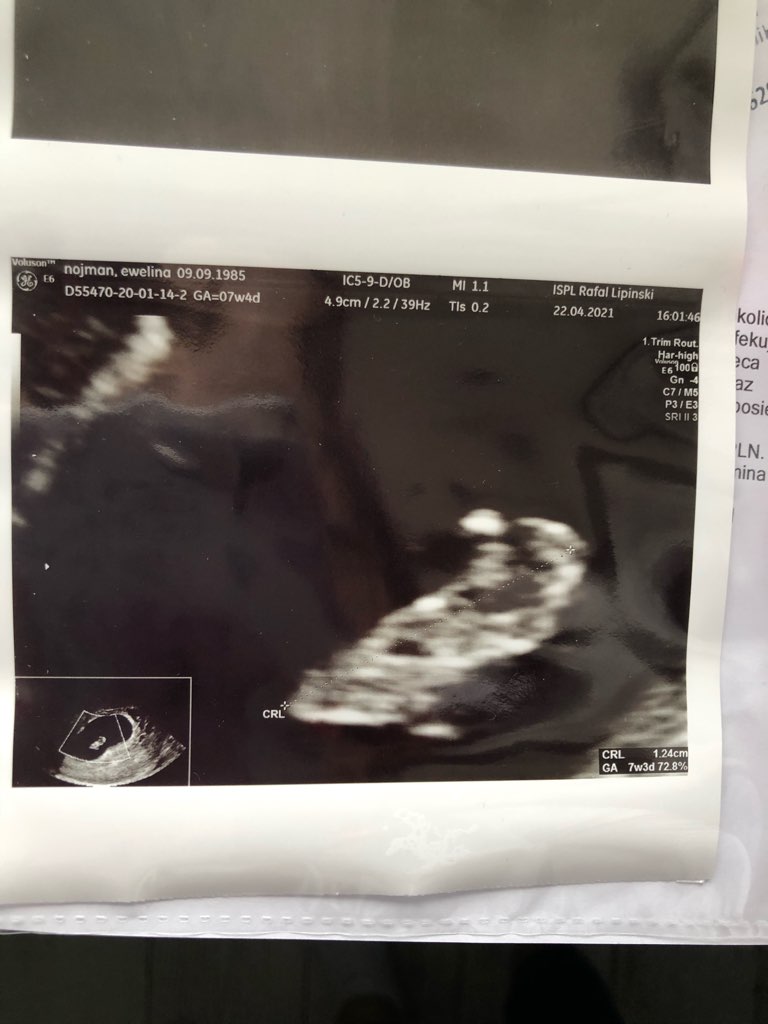

teraz jestem szczeliwa bo zadbał o mnie jak powinien ... dzidzia rośnie

A na kiedy masz termin?Hej! Ja już po dzisiejszej wizycie! Serduszko pieknie bije , maluszek ma już 11 mm i wychodzi ze jestem 7+1 tygodniu.

najważniejsze ze rośnie